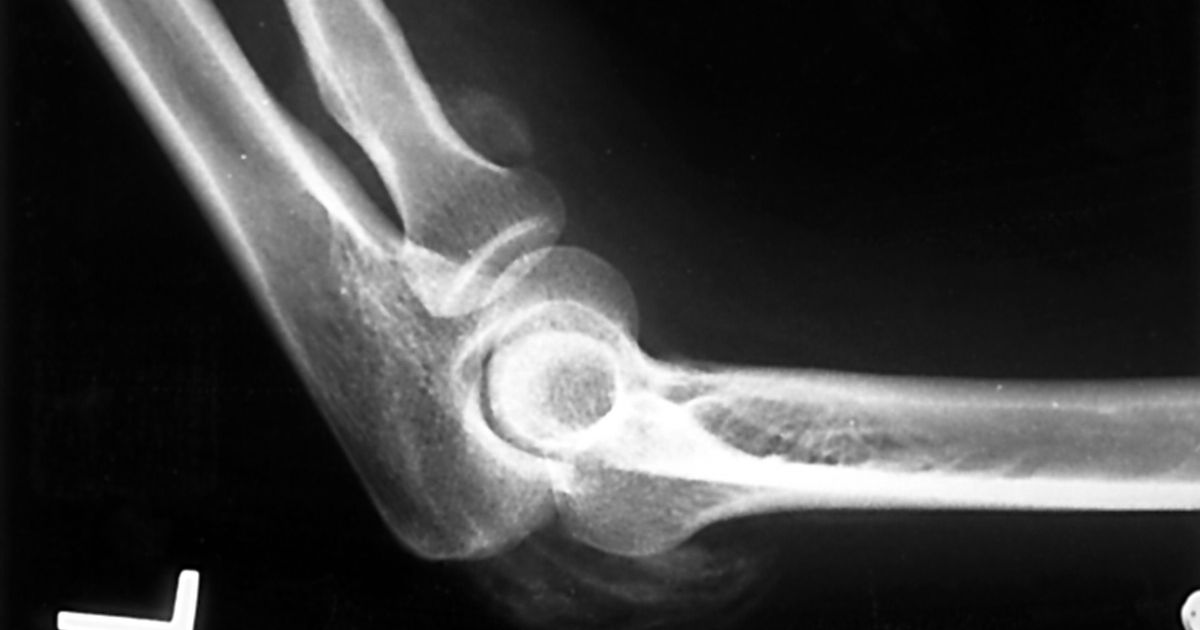

Ossification

Ossification is the process of cartilage or fibrous tissue ossifying and turning into bone. Ossification is very painful and can limit the range of motion and movement. Aside from being a symptom of fibromyalgia, ossification can also be caused by genetics and trauma and injury to an area of the body.

Ossification can be treated by resting the affected muscle, icing for fifteen to twenty minutes at a time, compressing the area, elevating the injured limb to help drain excess fluid, and by gentle stretching. Anti-inflammatory medications and orthotics may help, along with physical therapy.